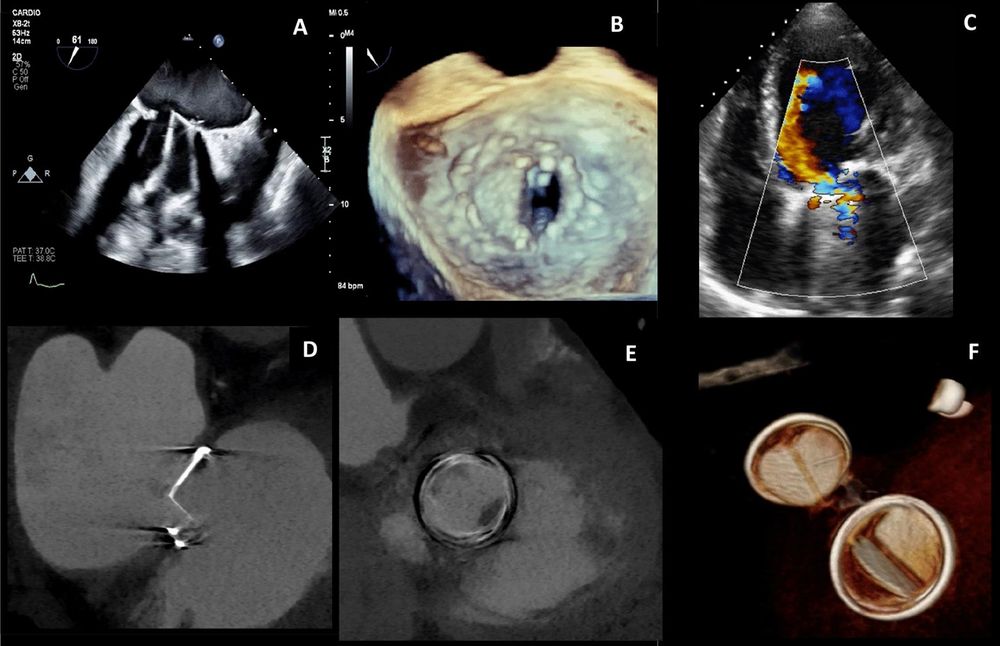

Discover how Duarte et al are advancing field with🌟A challenging case of prosthetic mitral valve dysfunction➡️value of multimodality imaging: now featured in #IJCVI 🌐 doi.org/10.1007/s105...